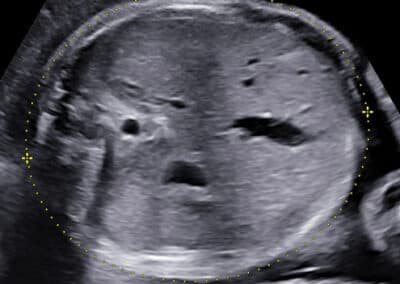

Ultrazvukové vyšetření provádíme přes břišní stěnu. Močový měchýř maminky nemusí být naplněný, miminko je totiž již vysoko v břišní dutině.. Určíme uložení a stav placenty, množství plodové vody a počet cév v pupečníku. Změříme velikost příčného průměru a obvodu hlavičky, obvod bříška, délku stehenní kosti a vyšetříme podrobně všechny orgány miminka. Pokud nebudete znát pohlaví miminka a budete si ho přát vědět, rádi vám jej sdělíme. Budete-li si přát připojit 3D-4D ultrazvukové vyšetření s reálným zobrazením vzhledu miminka , rádi jej připojíme. Při vyšetření se řídíme zásadami Fetal Medicine Foundation a všichni lékaři mají FMF certifikát na všechna ultrazvukové vyšetření ve druhém trimestru.

Vyšetření obvodu hlavičky

stav placenty a její umístění v děloze množství plodové vody změříme příčný průměr a obvod hlavičky, obvod bříška a délku stehenní kosti miminka a vypočítáme hmotnost miminka vyšetříme znovu všechny orgány miminka při významném zpomalení růstu miminka připojíme ten samý den k vyšetření i Dopplerovské vyšetření stavu krevního oběhu placenty a plodu